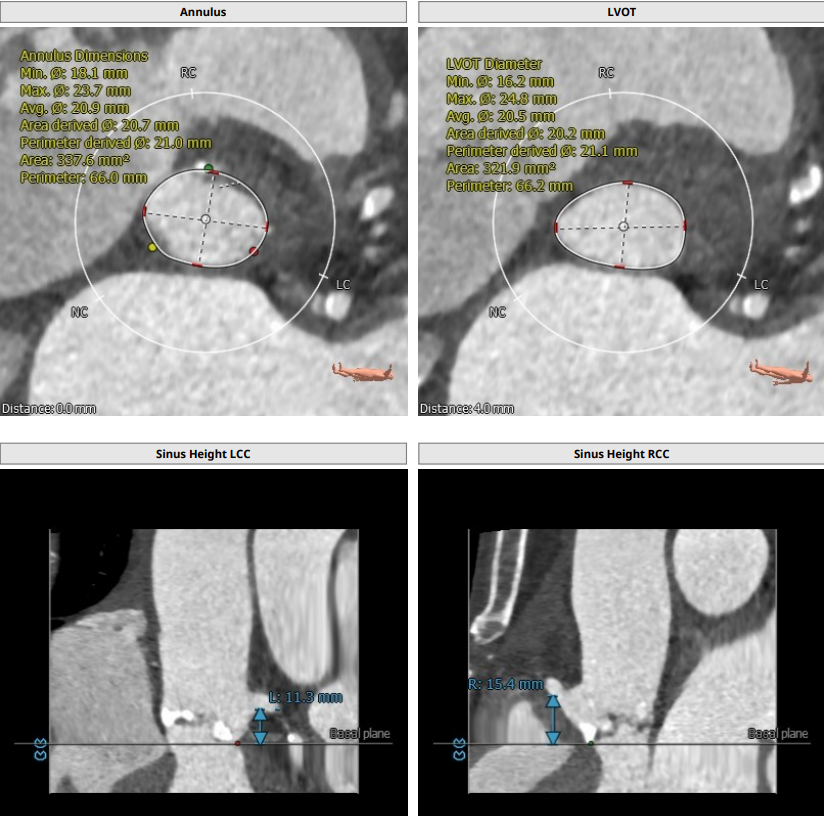

病人为三叶瓣,重度钙化,瓣环径为21,LVOT21.1,左冠高度11.3,右冠15.4,瓦氏窦均径在27左右,STJ26.3,升主无明显扩张,整体结构偏小,术前经综合评估,使用18F艾普特大鞘,venusA23号瓣膜预装。